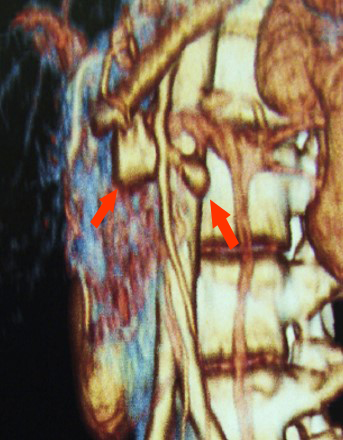

NF-1参考症例 31歳女性

• 腹痛、ショック

• SMAに2つの瘤、破裂の疑い

• カバードステントで止血